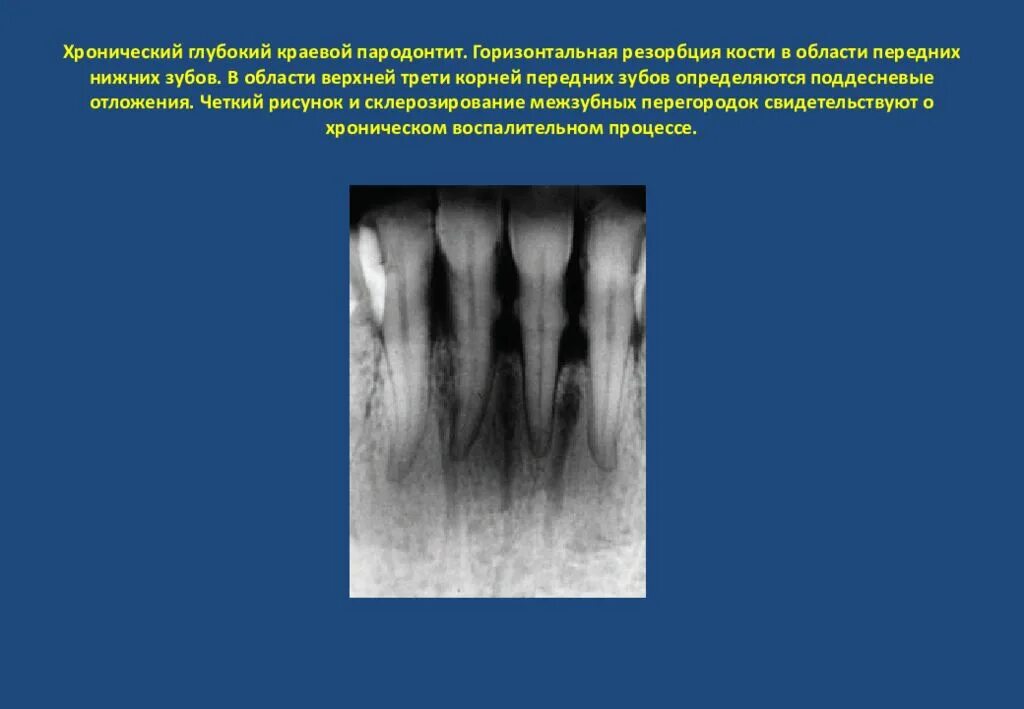

Резорбция ткани